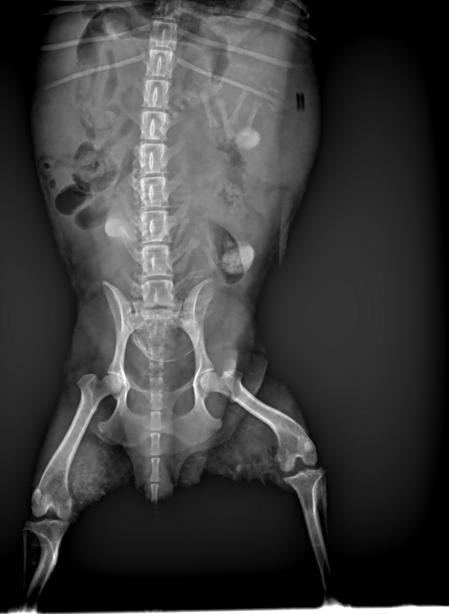

DR显示

6个胎儿胎位不正后脚朝下

编辑

初步诊断

狗狗同时两个胎泡流出,

DR显示有可能两个胎儿堵在阴道上端,

建议家长为狗狗选择剖腹产手术。